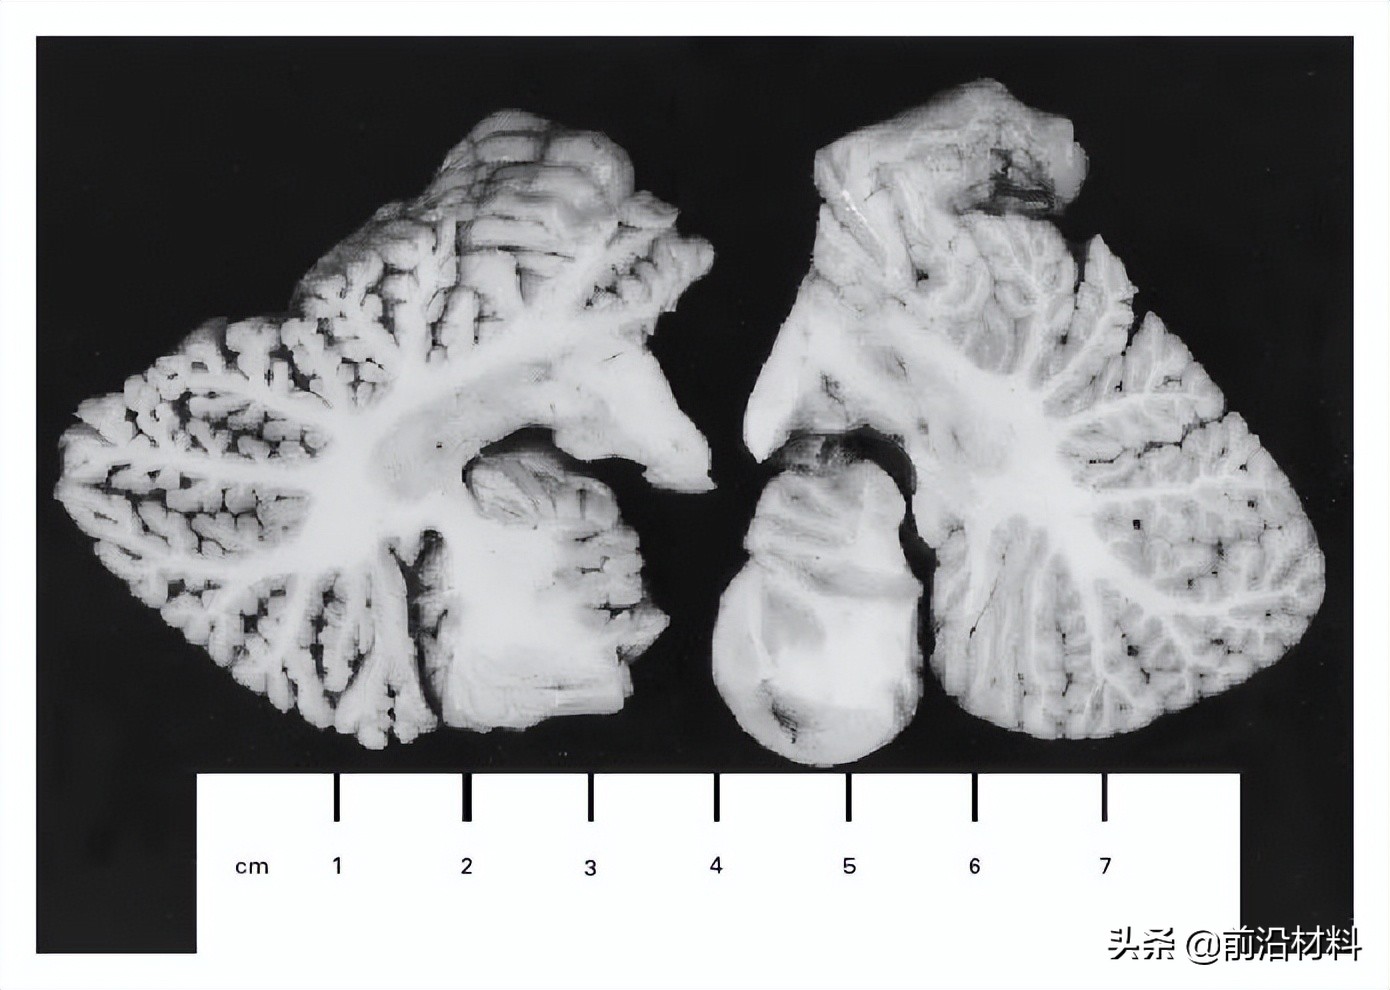

1997年6月8日,暴露于二甲基汞的第298天,凯伦·维特哈恩离世,终年48岁。尸检结果发现,她的大脑皮层变薄到只有3毫米。距状裂(位于枕叶内侧)周围的视皮层、与听觉性语言功能有关的颞上回的上表面均严重胶质化。在大脑双侧半球初级视觉和听觉皮层中,出现了大量神经元丢失和神经胶质细胞增生。她的运动和感觉皮层也出现了类似情况。小脑弥漫性萎缩,其中颗粒细胞、浦肯野细胞、篮细胞均有广泛丢失,小脑表层的平行纤维也丢失了。

维特哈恩的小脑半球(左)与普通女性的小脑半球(右) (图片来源:NEJM报告)

在她的额叶和视皮层、肝脏、肾皮质中,汞含量极高。她的大脑汞含量是从未接触过汞的尸检样本的600-1500倍。